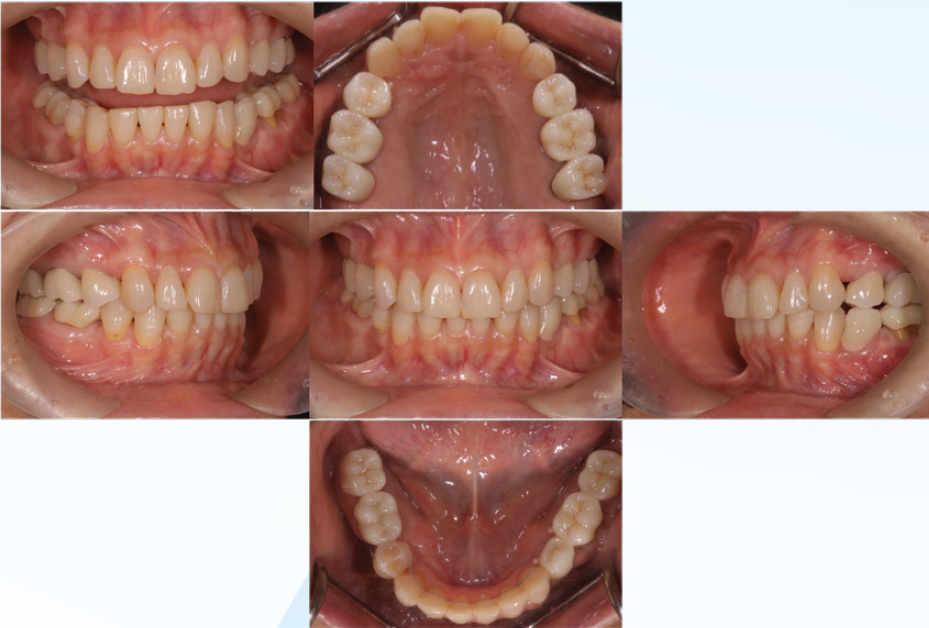

(図23) 最終補綴装置装着時

プロビジョナル・レストレーション装着期間に

得られた情報を基に最終補綴装置を作成